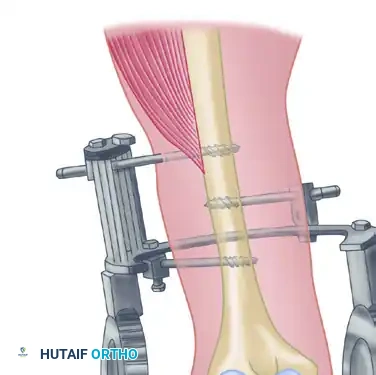

Step 3: Triceps V-Y Lengthening

Beginning proximally and using sharp dissection, reflect the aponeurosis of the triceps distally to form a flap of tissue that remains attached to the olecranon.

To perform the V-Y lengthening:

* Begin 7.5 cm proximal to the joint.

* Make an inverted "V" incision in the midline of the arm through the fibers of the triceps muscle, extending distally toward the olecranon.

* Curve this deep incision around the lateral edge of the olecranon to meet the distal end of the skin incision.